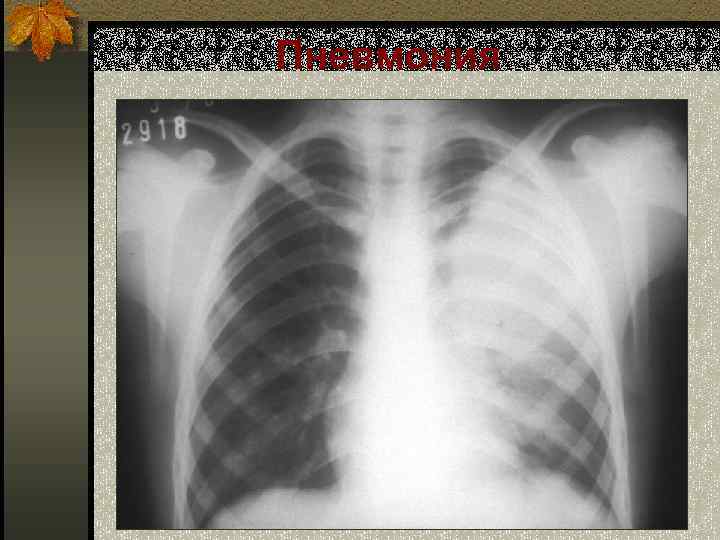

Пневмония